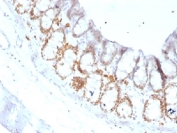

IHC testing of FFPE rat colon with FOXA1 antibody (clone FOXA1/1519). HIER: boil sections in 10mM Tris with 1mM EDTA, pH9, for 10-20 min.